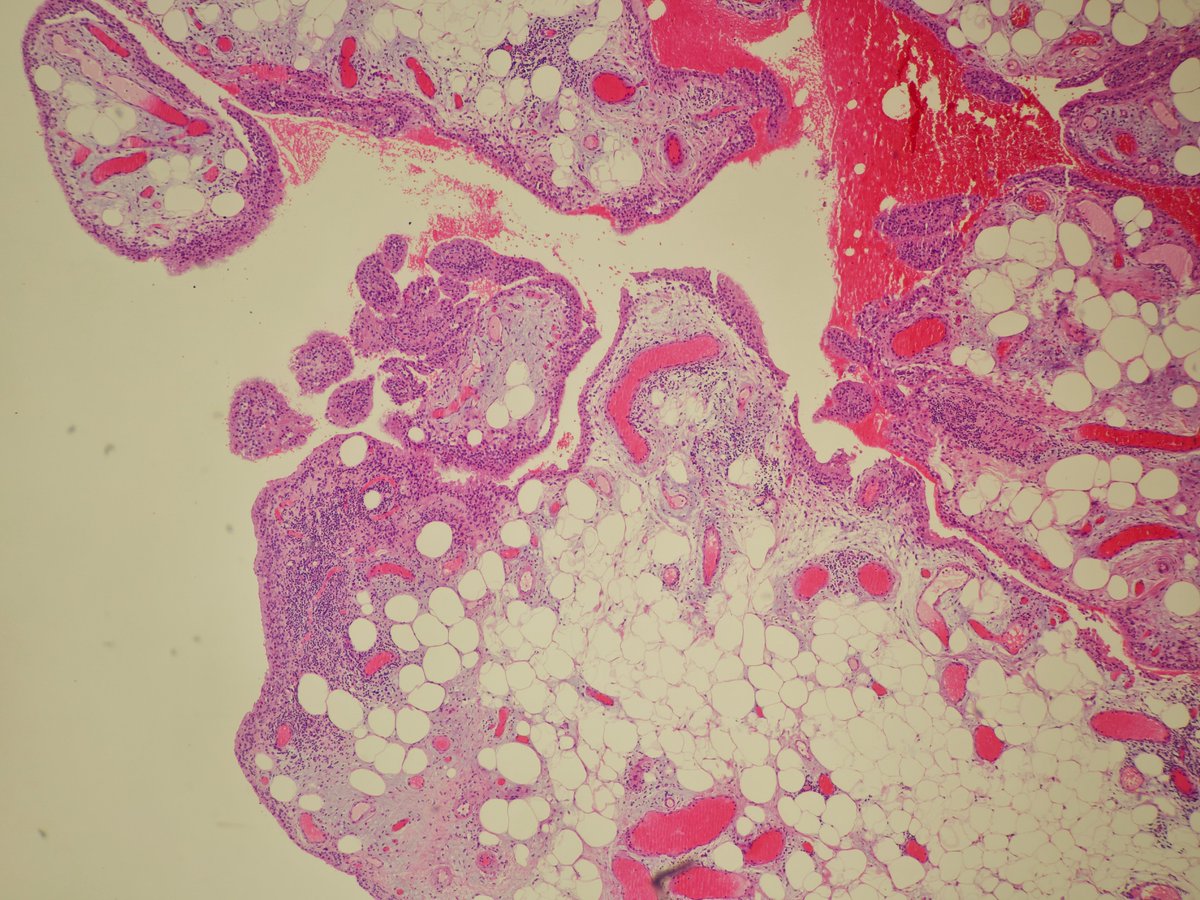

Not every epithelial tumor with papillary structures on the digit is an adenocarcinoma 🤔

Immunohistochemistry can help establish the diagnosis of hidradenoma with papillary structures.

doi: 10.1097/DAD.0000000000002291

by @JCandidoXavier

#ISDPDenver2026 #Path #pathology